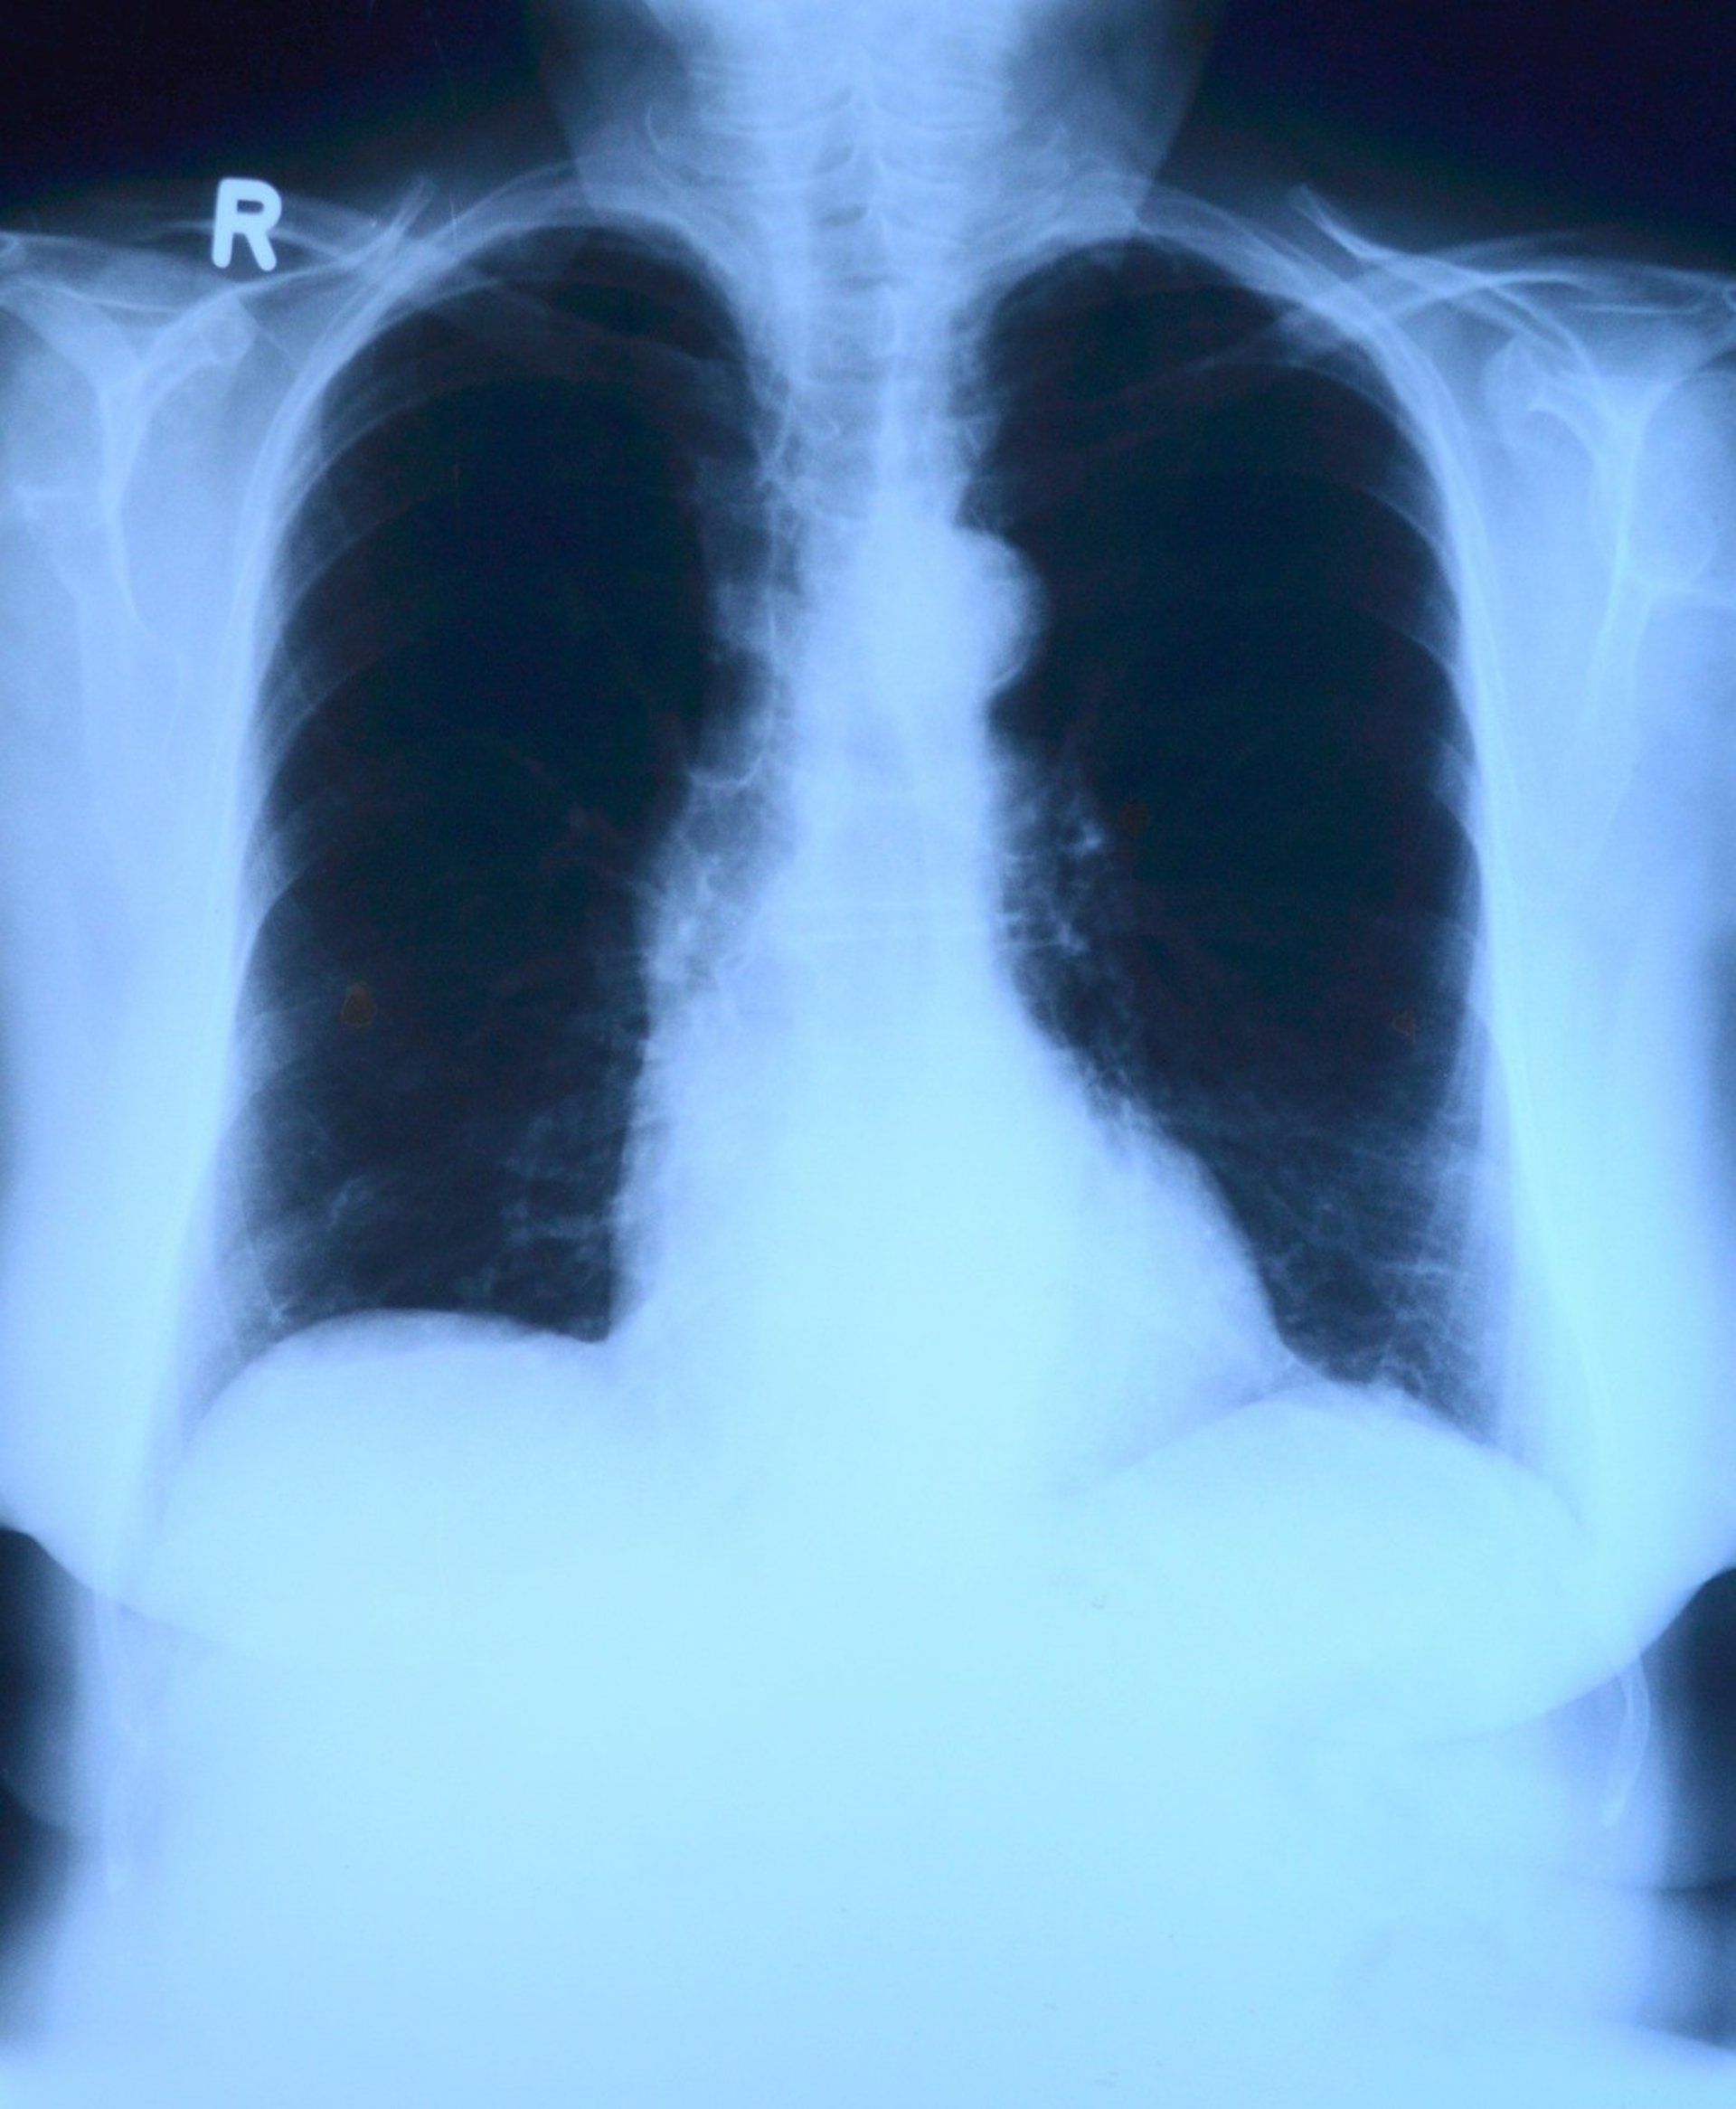

Identifican una vía de señalización 'farmacológica' que estimula la reparación d - PIXABAY/TOUBIBE - Archivo

Enfermedades como la neumonía, la gripe y el SDRA, una de las complicaciones conocidas de COVID-19, pueden dañar el revestimiento de los sacos de aire en los pulmones, conocido como epitelio alveolar, que evita que el oxígeno pase de los pulmones al torrente sanguíneo y puede provocar a muerte.

Los pacientes con COVID-19 que desarrollan SDRA enferman críticamente y, hasta la fecha, no se han desarrollado medicamentos específicamente para tratarlo en estos pacientes. Comprender qué objetivos y vías genéticos están involucrados en la regeneración del tejido epitelial es fundamental para desarrollar terapias efectivas para el SDRA y afecciones similares.